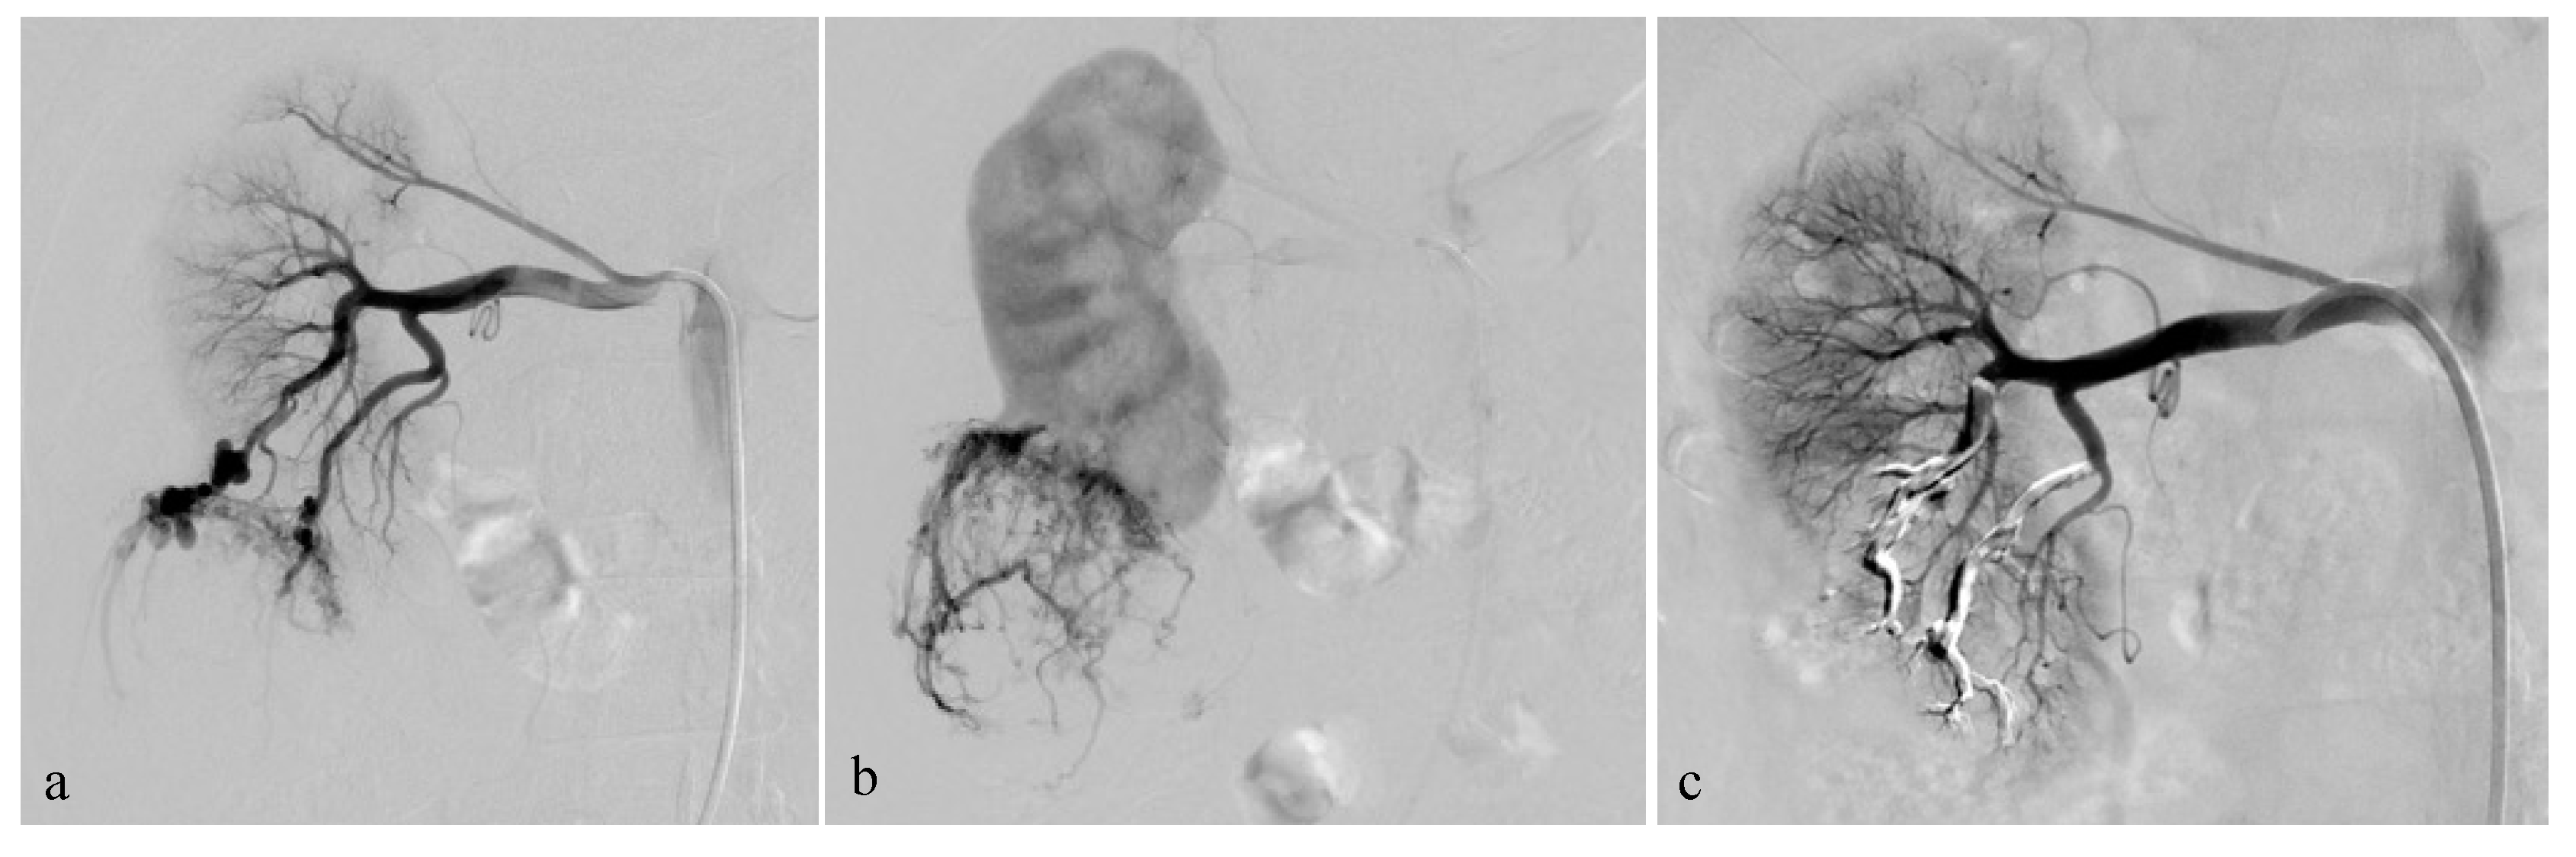

Figure 2.

Selective arterial embolization (TAE) of a large right AML. (a) Angiography shows two feeding arteries to the AML with multiples aneurysms. (b) The hypervascularity and dysplastic vessels of this AML are typical. (c) Final control after TAE of two arterial branches with ONYX 18 (6% EVOH) with technical success (lack of opacification of the AML).

The procedures were generally performed under general anesthesia or hypnosedation at the anesthesiologist’s discretion. Systemic anticoagulation was achieved during the procedures with intraarterial heparin in 3000-IU bolus injection, except during emergency procedures. TAE was planned during hospitalization for minimum 24 h. Before undergoing embolization, patients received 1 g of cefazolin (Ancef; GlaxoSmithKline, Philadelphia, Pennsylvania) to prevent superinfection of renal infarction associated with embolization. The right or left common femoral artery was punctured under ultrasound imaging, and a 6-French (Fr) sheath was introduced by Seldinger technique. An aortogram was obtained first through a 6-Fr guiding sheath to locate the renal arteries and to identify any accessory renal arteries or extra-renal feeding arteries. Selective renal angiography was then performed to assess the vascularization of the AML (Figure 2a,b), extension of tumor vessels outside the normal nephrogram, and vessel displacements by the tumor, as well as to identify aneurysms (Figure 2a). In patients with severe bleeding, active extravasation, and retroperitoneal blood were identified. Then, superselective catheterization of the AML feeding vessels was achieved to spare as much renal parenchyma as possible, using a coaxial 2.0 microcatheter with dual marker bands (Echelon®; Micro Therapeutics, Inc.® 2005), as well as an Onyx-compatible microcatheter. The dead space of the microcatheter was meticulously flushed with dimethyl sulfoxide (DMSO) solvent to avoid early polymerization of the Onyx in the lumen of the catheter. Onyx (6% or 8% EVOH) was injected at a steady rate of 0.16 mL/min firstly, whilst the dead space was being filled, to avoid development of vasospasm due to DMSO [18]. The EVOH concentration (6% or 8%) was arbitrarily chosen based on our experience with tumor devascularization, considering that the lower the concentration of the copolymer, the less viscous the agent is, allowing a more distal embolization. A total of 6% EVOH was preferably used (88% of AML). If check angiography identified other feeding vessels, further superselective catheterization and embolization were performed. The injection was continued and repeated until the distal end of the feeding arteries of the AML and their dysplastic portions were completely occluded. The endpoint of the procedure was complete devascularization of the tumor (Figure 2c), except when small branches cannot be catheterized (vessel diameter under 1 mm), which was specific to the individual vascular anatomy and clinical situation.

The average arterial pedicle per AML was 1.4 (±0.8). Arterial pedicle count was the number of angiographically visible arterial pedicles that were a direct division of the renal artery and participated in the vascularization of the tumor. A high arterial pedicle count was significantly predictive of a second embolization (p < 0.01). The mean pre-embolization volume was 201.1 (±504.1) mm3. The majority of angiomyolipomas were exophytic (96%, n = 24). Ten patients had aneurysms on angiography (Figure 2a and Figure 3), including only five seen on pre-embolization imaging at diagnosis (Figure 1). Table 2 presents the different AML characteristics.